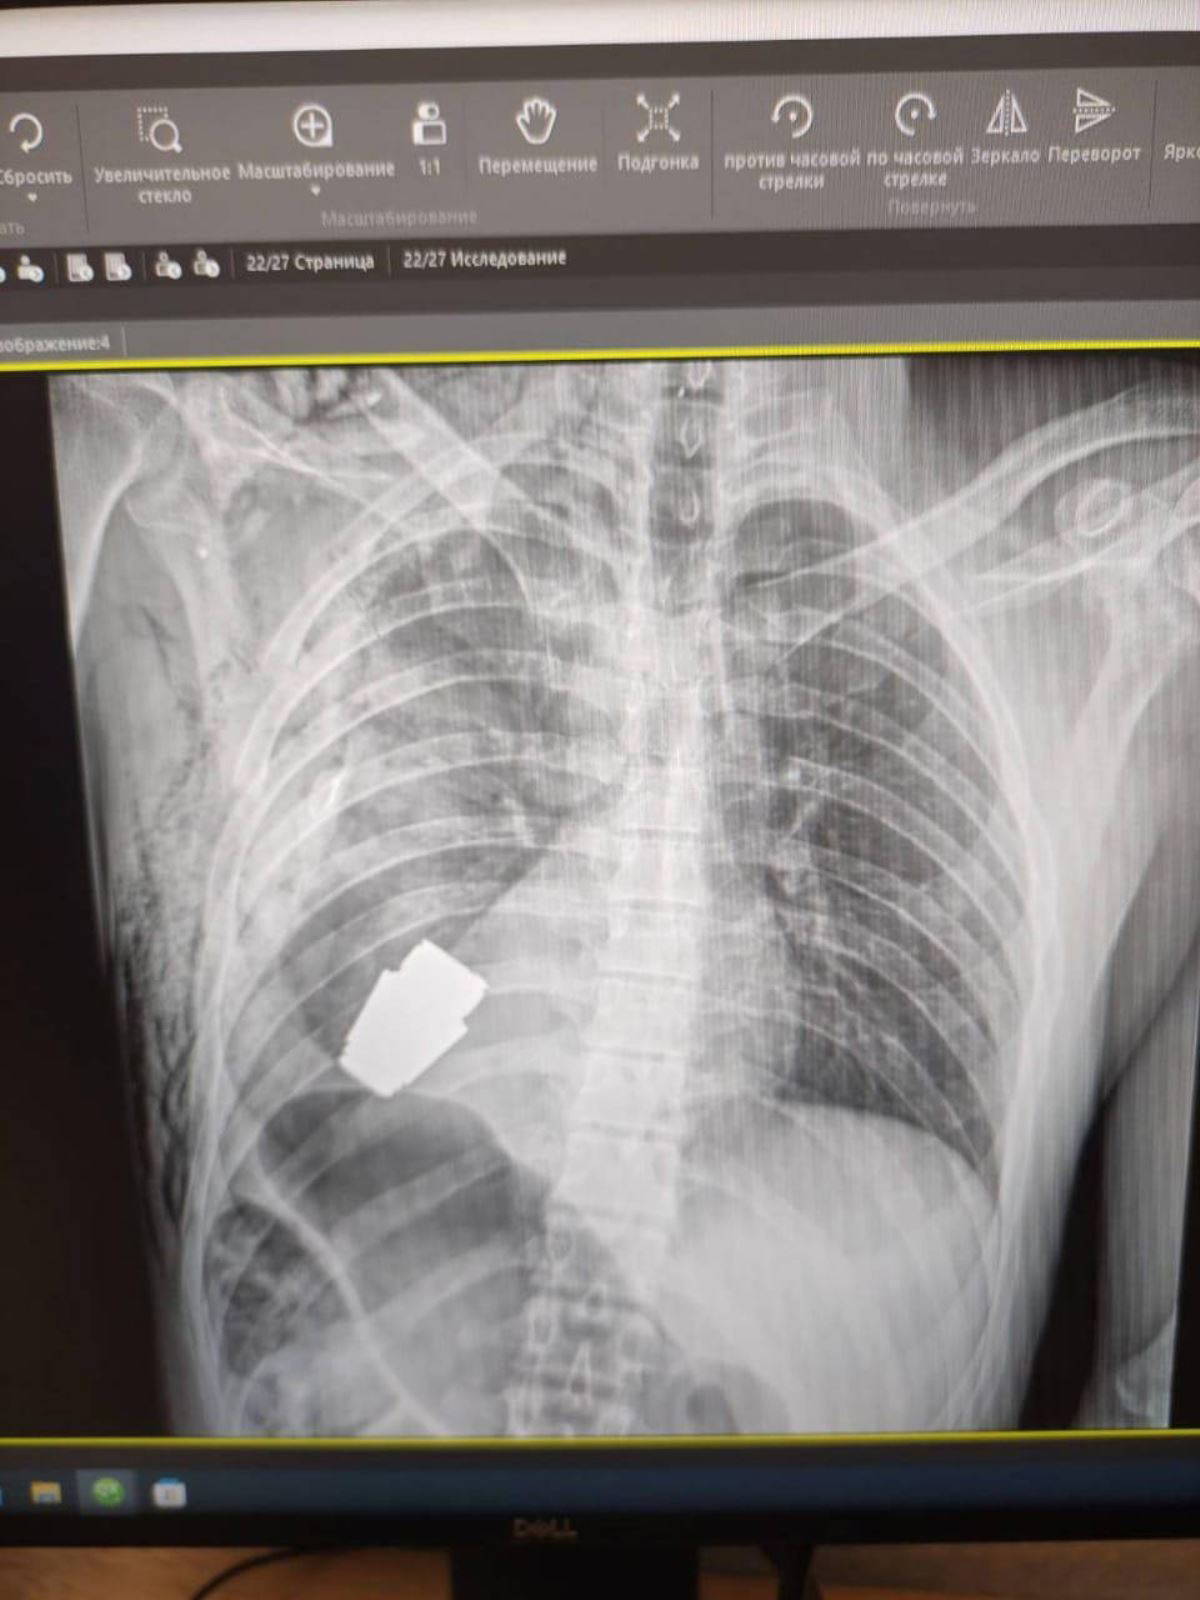

Ukrayna'da bir askerin kalbine yakın bölgesinde patlamamış VOG el bombası tespit edildi.

Bombanın her an patlayabilme ihtimali olduğu için Ukrayna Silahlı Kuvvetlerinin en deneyimli cerrahlarından biri olan Andrii Verba tarafından acil bir operasyon gerçekleştirildi. Ukrayna Savunma Bakanı Yardımcısı Hanna Maliar, cerrahi müdahalenin başarılı olduğunu ve askerin tedavi altına alındığını söyledi.

El bombasının askerin vücuduna nasıl girdiğine dair ise açıklama

yapılmadı.